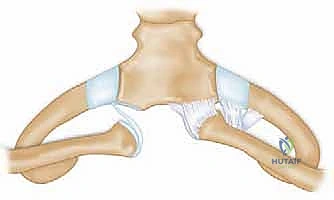

منظومة الأربطة المثبتة (حجر الأساس في الاستقرار)

بما أن العظام لا توفر الاستقرار، يعتمد المفصل بنسبة 100% على شبكة معقدة وقوية جداً من الأربطة:

- الأربطة الكبسولية (Capsular Ligaments): تغلف المفصل بالكامل. الكبسولة الخلفية هي البطل الحقيقي هنا، فهي أقوى المكونات والمثبت الأساسي الذي يمنع الترقوة من الانزلاق للأمام أو للخلف.

- الرباط بين الترقوتين (Interclavicular Ligament): يمتد بين الترقوتين عبر أعلى القص، ويعمل كجسر توازن يمنع هبوط الكتف.

- القرص المفصلي (Intra-articular Disc): قرص غضروفي ليفي يعمل كممتص للصدمات ويفصل المفصل إلى تجويفين، ويمنع اندفاع الترقوة للداخل نحو الرقبة.

- الرباط الضلعي الترقوي (Costoclavicular Ligament): رباط قوي جداً يربط أسفل الترقوة بالضلع الأول، وهو المثبت الرئيسي الذي يقاوم سحب العضلات للترقوة إلى الأعلى.